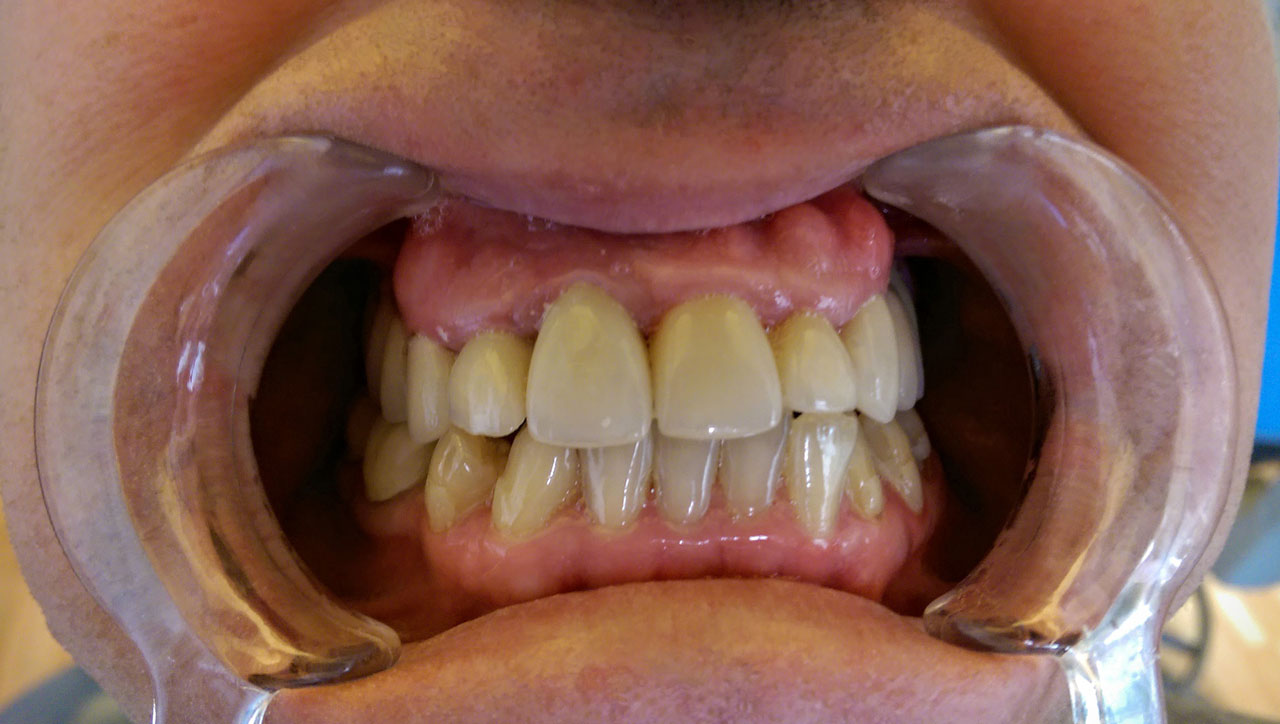

Alsó állcsont teljes rehabilitációja 72 óra alatt, azonnal terhelhető implantátumokkal súlyos paradontitisben szenvedő dohányzó páciens esetében. Az alsó állcsont fogai mind mozogtak az előrehaladott fogágypusztulás miatt.

A fogakat eltávolítottuk, a gyulladt, fertőzött csontot kitakarítottuk, kifertőtlenítettük, majd azonnal implantáltunk.

Svájci, IHDE márkájú, azonnal terhelhető implantátumokat helyzetünk be, és ezekre harmadnapra rögzített, hosszútávú, fémvázas, esztétikus műanyaggal leplezett hidat ragasztottunk be.

Ezt az ideiglenes hidat a sebek gyógyulása miatt használjuk, de tartóssága miatt véglegesként is használható. A legtöbb esetben, ahogy itt is, 6 hónap múlva porcelán hídra cseréljük, a teljes gyógyulás után.